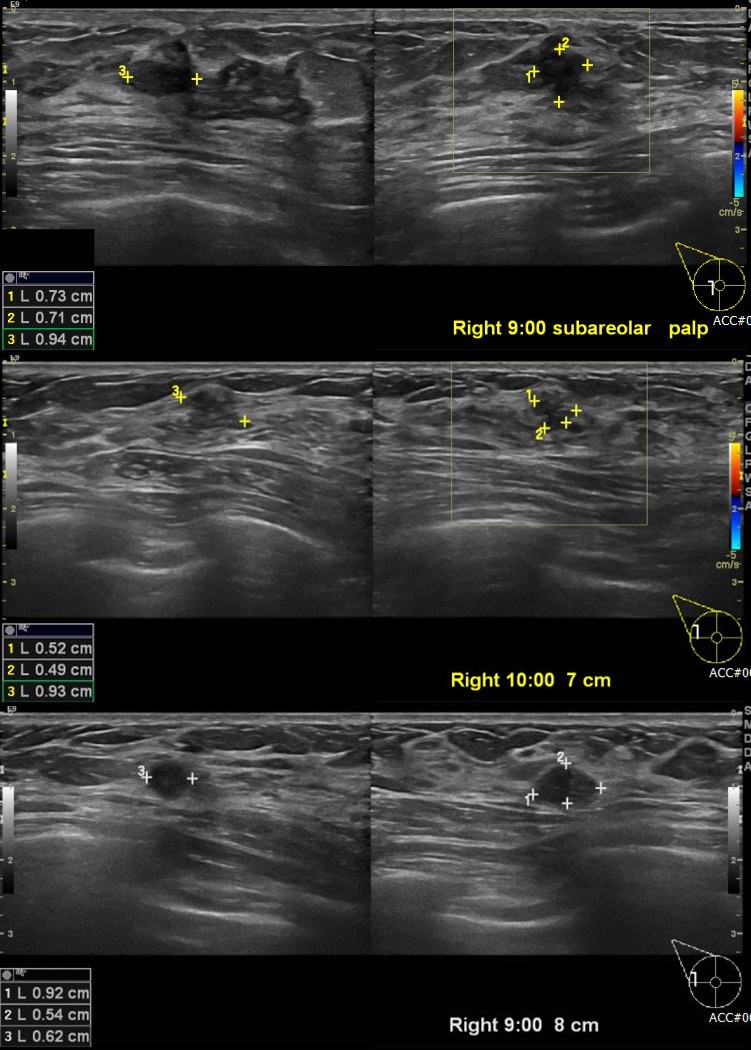

상기환자 유측 유방에 만져지는 멍울로 내원하신 40대 여성분으로 우측 유두 및과

우측 9시 10시 방향에 만져지는 멍울 각각 조직검사 시행하여 우측 침윤성 유관암 진단되습니다.